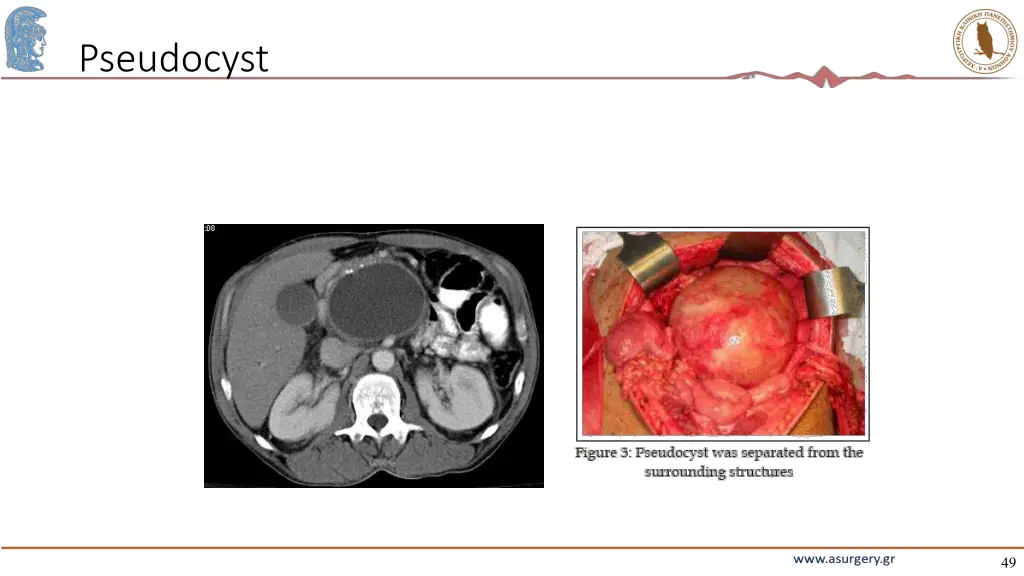

49. Pseudocyst 49